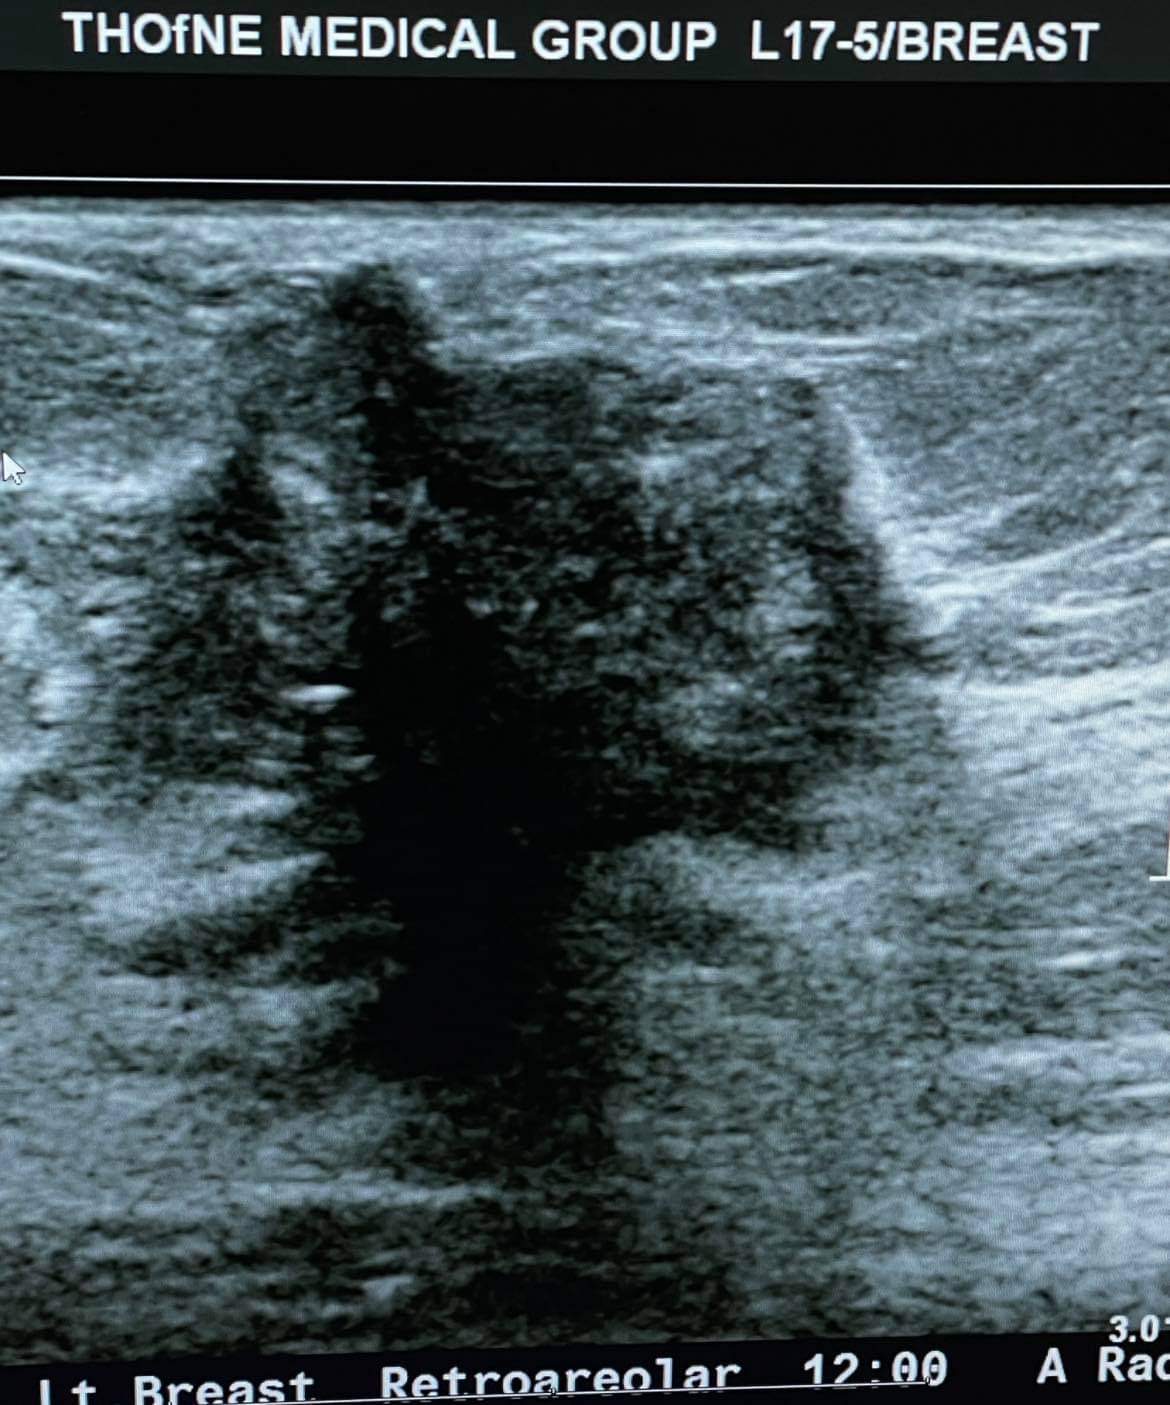

Tu cijelu godinu grudi su me jako svrbjele. Lijeva bradavica u dojke se povlačila unutra a ja sam sve to ignorisala. Pominjala sam sestri, mami, pa čak i mužu. Napokon, krajem decembra 2021. godine, mama se na mene doslovno izgalamila s onim našim “ ko će te čuvati ako nećeš samu sebe” i pod pritiskom zakazala sam termin. Čim sam otišla kod ginekologa sutradan, dalje me je poslala u bolnicu na pregled, a nakon toga i na biopsiju.

Tu cijelu godinu grudi su me jako svrbjele. Lijeva bradavica u dojke se povlačila unutra a ja sam sve to ignorisala. Pominjala sam sestri, mami, pa čak i mužu. Napokon, krajem decembra 2021. godine, mama se na mene doslovno izgalamila s onim našim “ ko će te čuvati ako nećeš samu sebe” i pod pritiskom zakazala sam termin. Čim sam otišla kod ginekologa sutradan, dalje me je poslala u bolnicu na pregled, a nakon toga i na biopsiju.

Ja imam rak dojke, lijeve, i imam rak limfni čvorova isto na lijevoj strani.

Doktorica mi je odmah rekla da mi neće moći spasiti bradavicu i naravno da će mi grudi ostati poprilično unakažene i da ih mora odstraniti gotovo 90%. Druga operacija je uklanjanje limfnog čvora gdje je rak, ispod pazuha. Nije me to uopšte potreslo, jer su to samo riječi, ali onaj dan kada sam vidjela stotine slike kod plastičnog hirurga drugih žena kojima se isto desilo, htjela sam vrištati. Samo sam šutjela i mahala glavom na sve što je govorio, a nemam pojma ni šta mi je rekao. Stotine slika mi je pokazao kako će to sve izgledati poslije operacije kad se ukloni rak. Znači prije radijacije i hemoterapije. Užas! Nisam plakala ali sam se upitala – zar se ovo stvarno dešava ili sam ja u nekoj noćnoj mori? Brzo sam se probudila dok je doktor trabunjao o proceduri o kojoj nisam zapamtila možda dvije riječi. Jedino znam da sam na kraju izašla iz kancelarije mrtva-hladna, totalno utrnula. Nisam uopće razmišljala više o hirurgu i brzo sam taj dan odlučila da ne želim rekonstrukciju grudi nego da mi se zaliječi rana pa tek onda nakon godinu ili kad već zarastu rane, tada ću pokrenuti te ostale rekonstruktivne procedure. Za sada prvenstveno želim da uklone rak s operacijom, radijacijom i hemoterapijom. Rekonstrukcija je meni lično kozmetička popravka koja je i nebitna, jer na kraju krajeva, ja se osjećam svakako sakata i to će tako biti do kraja mog života. Ovo go**o u meni vlada mojim tijelom, a ja ništa nemogu da poduzmem, ama bas ništa.